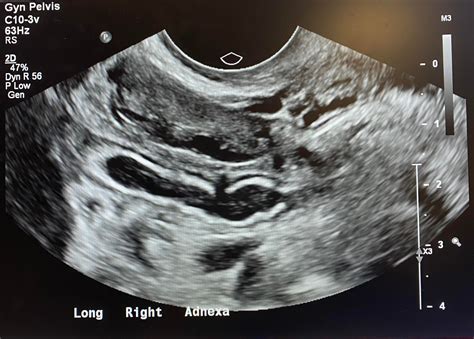

When performing an ultrasound to diagnose appendicitis, radiologists look for several key signs:

• Periappendiceal Fluid: The presence of fluid around the appendix can indicate inflammation or infection.